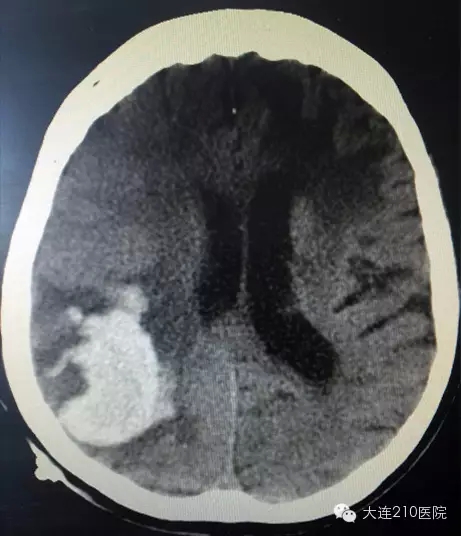

刘老太太已77岁,独居多年,虽已高龄,但生活仍可自理,入院三天前不明原因陷入昏迷,家属发现后立即送往第210医院就诊,排查头部CT发现颅内存在巨大血肿,病情危重,需要立即在全身麻醉条件下行开颅手术。

立体定向引流术前 头部CT发现颅内存在巨大血肿